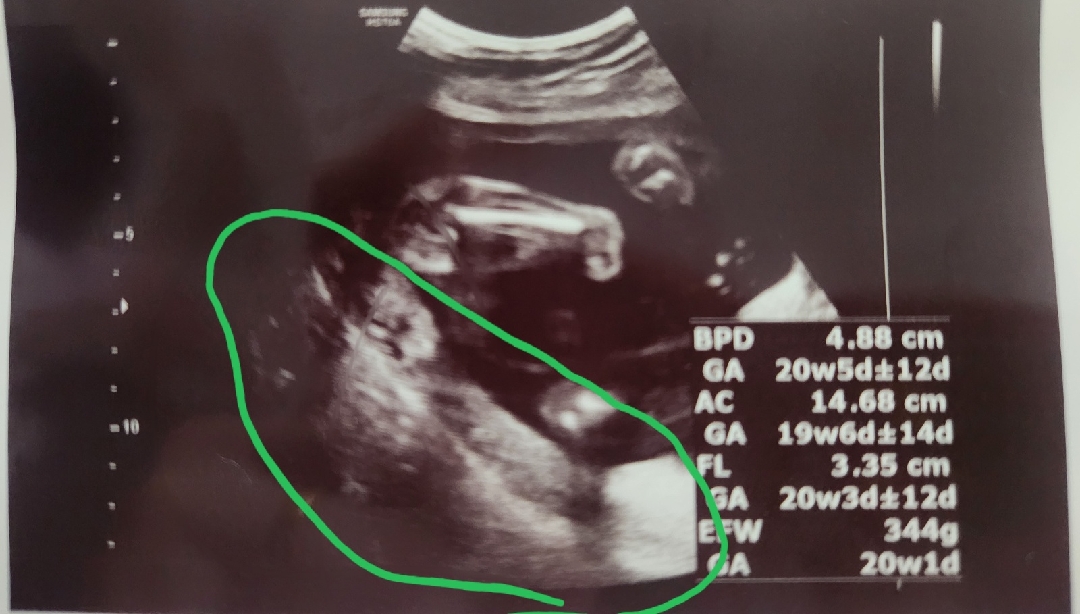

20주 쌍둥이임산부입니다 전치태반확정받았어요 병원에서는 수술할꺼고 피많이난다고 산모가딱히할껀없다고 후기엔 임신중독증올수있다 이야기듣고왔어요 ㅠㅠ걱정이 한가득이네요

저희는 20주 3일인데 금일 들었어요 전치태반이고 위험할수 있다 무거운거 관계 맺지 말라 등등 했는데 다른거는 이상없다고 하네요 아내가 많이 우울하고 자기 자책하길래 자기 책임 아니라고 했습니다 의사가 안좋게 말하고 상급병원가야하고 재왕절개 해야한다 전 무덤덤했습니다 무조건 병원은 최악만 이야기 하닌깐요 여러방면을 생각하세요 태반이 31주까지는 움직이니 많이 누워있고 태아가 커지면서 올라간다고 하니 의사마다 이야기 하는게 다릅니다 최악의 경우는 조심하고 낳으면 되고 최고는 긍정적으로 가지며 조심히 생활하고 4주뒤 보러 가면됩니다 긍정적으로 가지세요 다른 이야기 들으면 올라간 사람들이 많다고 하네요 80프로 이상은 올라가고 20프로는 아니지만(사람마다 달라서)그럴때 일수록 스트레스 받지말고 웃으며 생활이 중요합니다 단 피 비침 있으면 방문하라고 하니 그것만 조심하면 될듯해요

오늘 정기검진 받으로 갓다가 전치태반같다고 하셔서 너무 걱정이되네요 아직 정밀초음파는 안봣었요 오늘이 19주6일되는날이라 아직 확실하다고 말씀을 못하신데요 근데 선생님이 보시기에는 전치태반 같다고 ... 그래서 제가 혹시 바뀔수 있냐닌깐 저는 좀 심한편이라 안바뀌걸같다고 하셔서 너무 걱정입니다 혹시 저처럼 20주 다되서 전치태반이라고 이야기 들으신분 있을까요?ㅜㅜ